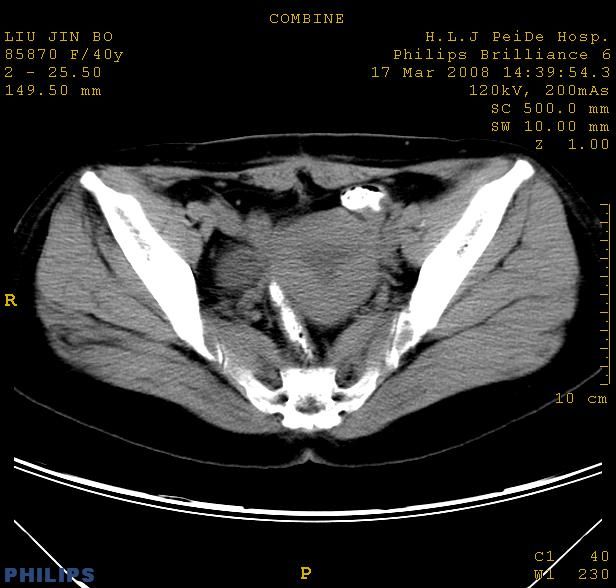

以下是引用qiuleiyu在2008-4-27 12:36:00的发言:[br]支持;右侧腰大肌后方神经源性肿瘤可能大,神经节细胞瘤?

以下是引用形影不离在2008-4-27 14:11:00的发言:[br]1.考虑右侧腰大肌脓肿。[br]2.左侧附件区炎症。[br]3.子宫增大,建议:进一步检查。